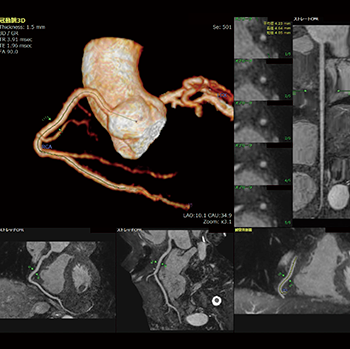

■Whole heart MRIに対する冠動脈自動抽出精度の向上

腎機能低下,低年齢層患者における被ばく線量を考慮し,形態情報の観察目的で非造影のwhole heart MRIが撮像される。V4.3から“冠動脈解析(MR)”において,高精度な心臓,冠動脈抽出機能を搭載している(図4)。冠動脈解析(MR)では,さまざまな画像パターンにおいて主要な血管を安定して抽出できるような抽出エンジンの開発をめざしている。

図4 冠動脈解析(MR)で主要3血管を抽出した画像例

右冠動脈(RCA)の各種CPRを表示している。